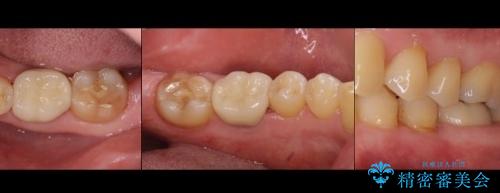

矯正治療後、右下のインレーブリッジおよび左下の銀歯のやりかえを行なっています。

右上の八重歯は、右上の奥歯を矯正用ミニスクリューを用いて遠心移動を行い解消しました。

下の前歯はIPR(エナメル質を薄く削り歯を小さくする処置)を行なっています。